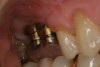

Fig 14. After unscrewing the abutment screw, the crown/abutment assembly is removed as one unit.

Figure 14

Fig 15. The tissue surface is finished and polished.

Figure 15